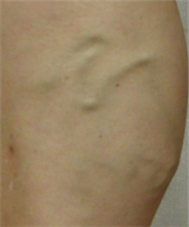

혈관은 아래의 사진들처럼,

아주 얇고 가는 실핏줄부터 지렁이 굵기의 튀어나온 혈관까지

다양한 모양으로 보일 수 있습니다.